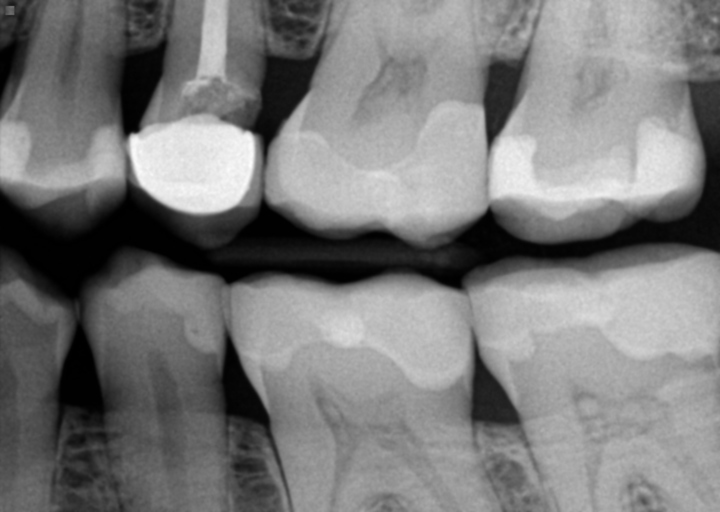

Unfortunately, metal dental crowns can interfere with your mris. Can be scanned with no problem or restriction. I have had many mris in the past few years without issue.

Having implants and/or crowns in your teeth is not a problem for the mri examination, but you need to wait 6 weeks after the implants / crowns are placed to go in the mri scanner. Do you know any people who have dental crowns and got the mri scan with them? Crowns made of porcelain, composite resin, or gold pose no risks from mri.

Dentistry is like art work, the porcelain crowns are made with a special combination of porcelain powders. Even so, it�s best to alert your doctor that you have dental implants if you need an mri. Metal objects in the body can still interfere with imaging even if there is a slim chance that they will injure you.

Permanent dental work containing metal may affect the imagequality. They vary in cost and durability but are widely available and do the same job as metal materials. No you should be fine!

Lam, thank you for your very informative article. The mri images of your mouth/cheeks could become a bit blurry, but it will not affect the examination. Crowns and bridges, again, should be cemented very securely so that they resist chewing forces, and i have a hard time believing that a conventional crown or bridge could have an issue with mri forces.

Dental implants and mri technologies continue to advance, which is good news for patients. The age of a crown may be a clue to the material used. Some metals, such as the titanium used to make dental implants , don’t interact with magnetic fields, but other metals, including nickel and gold, will respond when.

If a patient has a crown made with metal, or of porcelain fused to metal, they should consult their dentist before getting an mri.